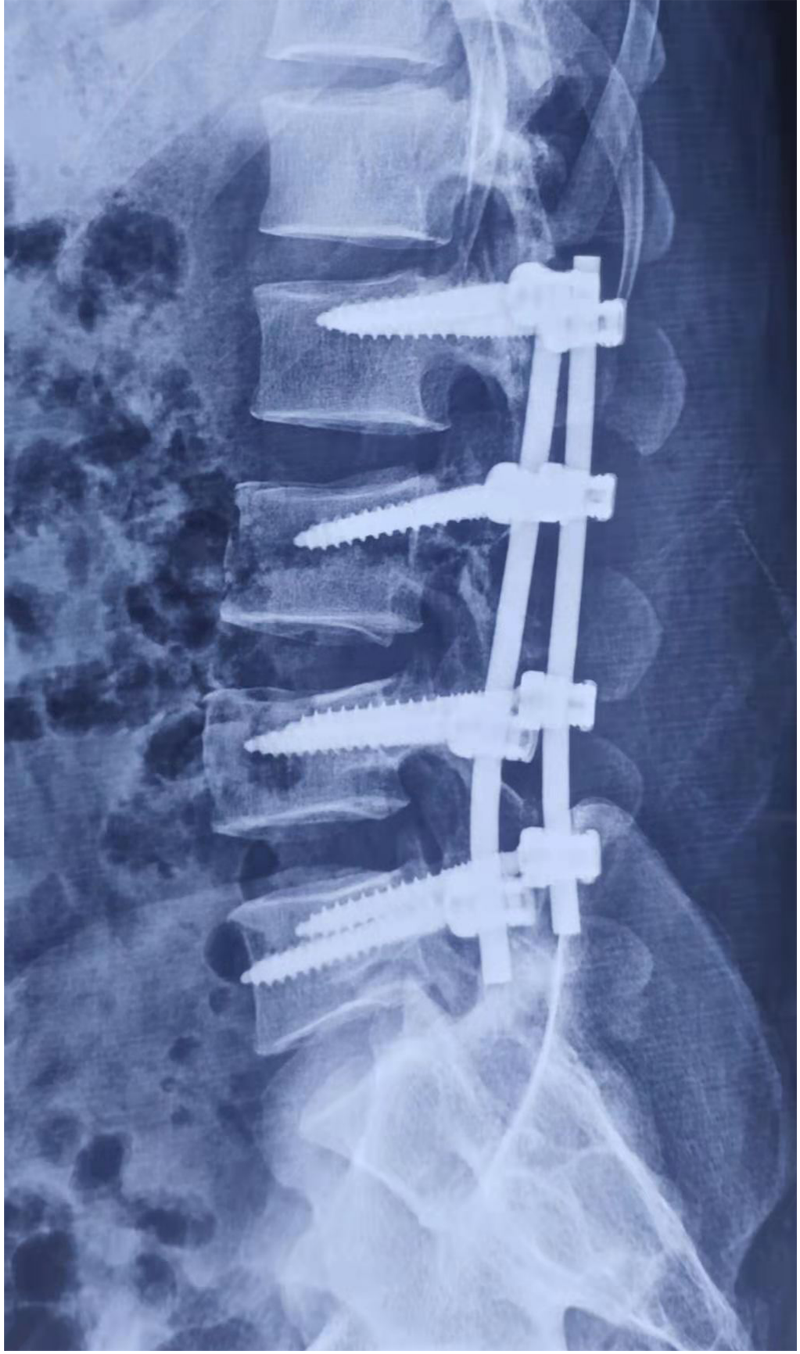

說起閆某的遭遇令人唏噓。他在礦井工作時,不幸被落下的碎石砸傷,導(dǎo)致胸椎、腰椎、肋骨、小腿多處骨折。由于病情危重從縣醫(yī)院轉(zhuǎn)往南京某醫(yī)院搶救,病情穩(wěn)定后經(jīng)歷了“后路胸椎骨折減壓復(fù)位植骨內(nèi)固定術(shù)”和“后路腰椎骨折切開減壓復(fù)位內(nèi)固定+左側(cè)腓骨骨折切開復(fù)位內(nèi)固定術(shù)”,身體里裝滿了螺釘鋼板。經(jīng)歷過生死考驗后,閆某第八胸椎以下感覺活動完全消失(雙下肢肌力0級,大小便失禁)。也就是醫(yī)學(xué)上說的“截癱”。閆某剛?cè)肟祻?fù)醫(yī)學(xué)科時,只能平躺,腰背部疼痛,雙下肢肌張力高,像“棍子”一樣僵直無法分開,輕輕觸碰就會抖動、痙攣。